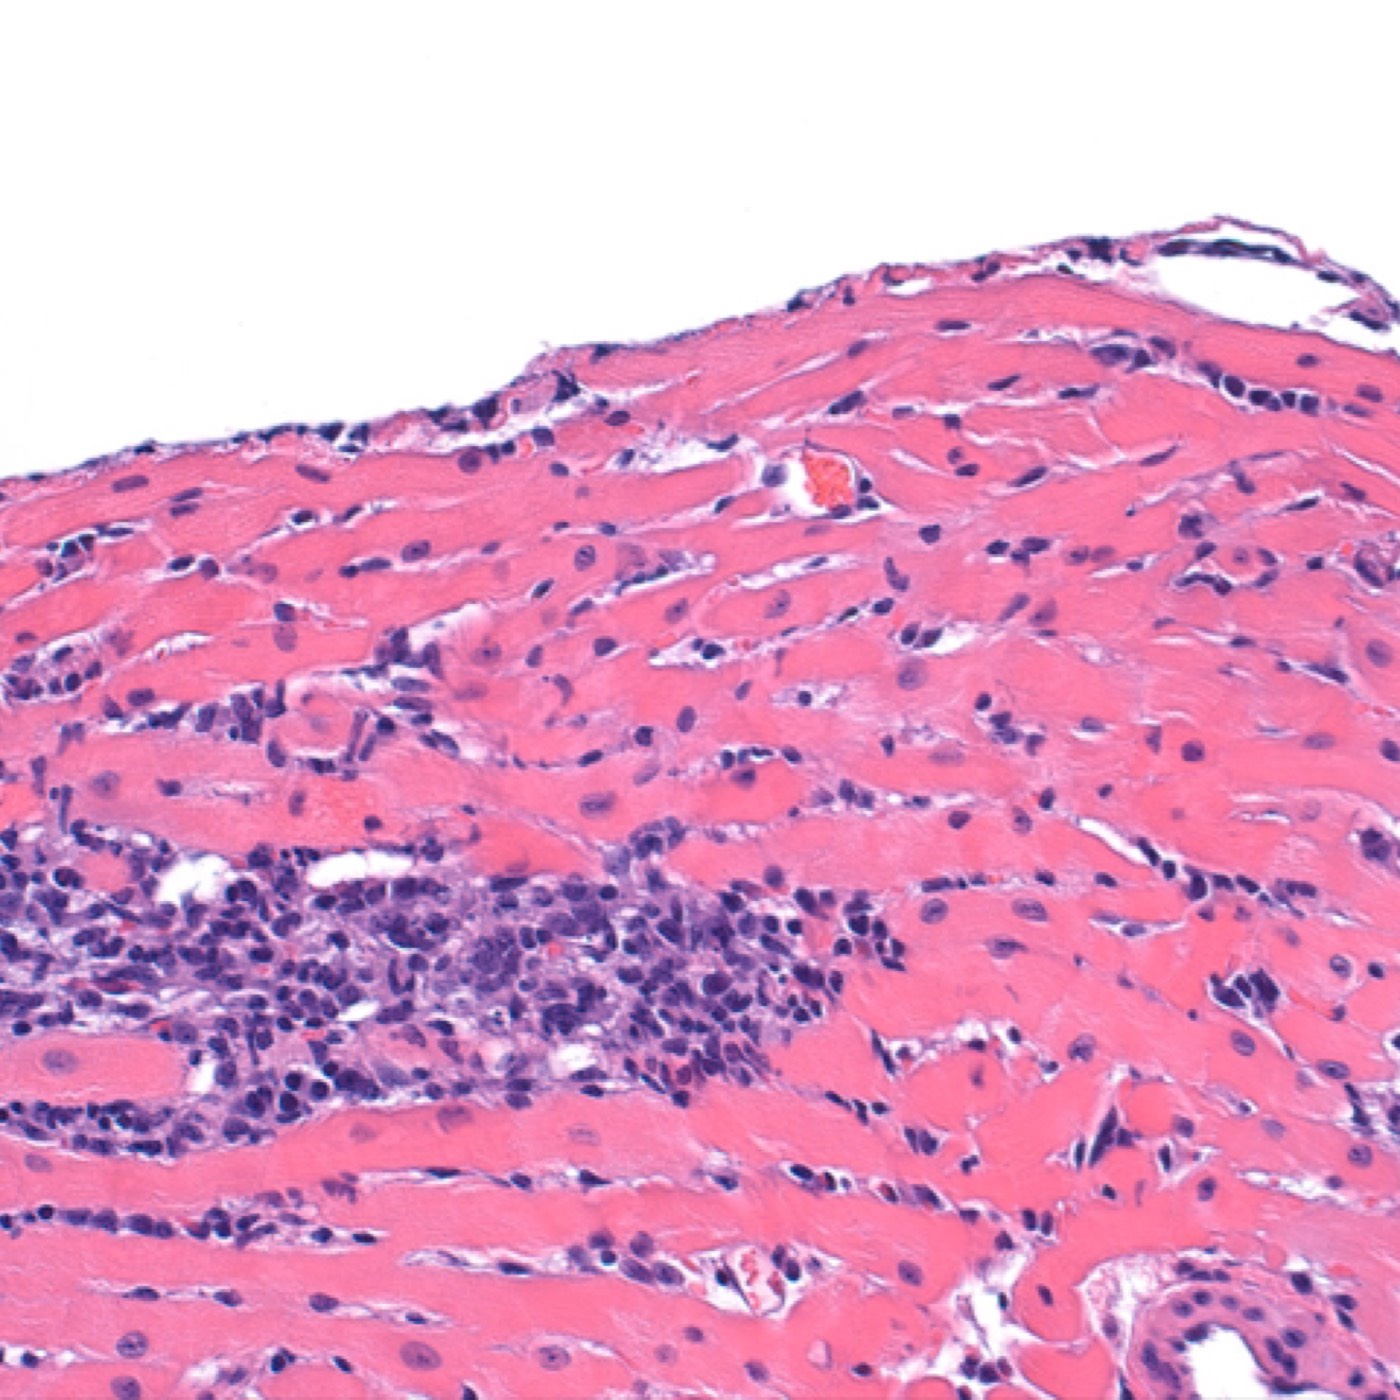

Contributor: Alec Coston, MD Case Report Summary: A 17-year-old female involved in a motor vehicle collision presented to a rural emergency facility via personally operated vehicle. During workup and initial CT scan, the patient began rapidly decompensating with CT revealing a 1.5cm epidural hematoma with 7mm of midline shift. The patient went from being able to walk and talk to being obtunded with a blown left pupil and unresponsive. Following intubation, the patient was being prepared for transport but potential delays required immediate emergency evacuation of the hematoma via a Burr Hole. A traditional Burr Drill was not immediately available at the facility, so an improvised Burr Drill using an Intraosseous (IO) drill was used. 35mL of blood was removed from the hematoma and the patient immediately improved from a GCS of 3 to GCS of 8. The patient was transferred to a higher level of care facility, extubated the following day, and made a full neurological recovery. Educational Pearls: What is an epidural hematoma? An epidural hematoma is a collection of blood between the dura mater (outermost layer of the meninges) and the skull, whereas a subdural hematoma is a collection of blood between the dura mater and arachnoid mater. Both can be life threatening depending on location and size. Epidural hematomas tend to be arterial, and are typically secondary to trauma and can rapidly expand, but with timely recognition and evacuation of the bleed, favorable outcomes are often possible. What are typical intracranial pressures and at what levels do they become pathologic? Typical intracranial pressure (ICP) varies by age, but past infancy and early childhood, adolescents and adults have a value typically between 8-15mmHg. Values exceeding 20mmHg become pathologic and rise exponentially with increased volume. Initial symptoms may include headache, nausea, and vomiting, but with increased pressures may progress to more life threatening symptoms such as loss of consciousness, cranial nerve palsies, pupillary constriction or dilation (sign of herniation), and respiratory irregularities. What is the takeaway in timing of epidural hematomas? Older studies show that evacuation of a hematoma with lateralizing features before the two hour mark of coma symptom onset is correlated with decreased mortality (ranging from 15-17%), but beyond 2 hours the mortality increases to well over 50%. Though mortality statistics have grown more variable, early targeted evacuation of epidural hematomas still remains critical for improved patient outcomes. In austere conditions with limited resources, improvisation with interosseous drills and needles can improve patient outcomes and achieve the target therapy for epidural hematomas. References Haselsberger K, Pucher R, Auer LM. Prognosis after acute subdural or epidural haemorrhage. Acta Neurochir (Wien). 1988;90(3-4):111-116. doi:10.1007/BF01560563 Hawryluk GWJ, Nielson JL, Huie JR, et al. Analysis of Normal High-Frequency Intracranial Pressure Values and Treatment Threshold in Neurocritical Care Patients: Insights into Normal Values and a Potential Treatment Threshold. JAMA Neurol. 2020;77(9):1150-1158. doi:10.1001/jamaneurol.2020.1310 Pisică D, Volovici V, Yue JK, et al. Clinical and Imaging Characteristics, Care Pathways, and Outcomes of Traumatic Epidural Hematomas: A Collaborative European NeuroTrauma Effectiveness Research in Traumatic Brain Injury Study. Neurosurgery. 2024;95(5):986-999. doi:10.1227/neu.0000000000002982 Summarized by Dan Orbidan, OMS2 | Edited by Dan Orbidan and Jorge Chalit, OMS4 Donate: https://emergencymedicalminute.org/donate/